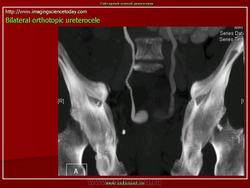

Продолжение.

Приложения:

1.u.slayd173.jpg2.u.slayd174.jpg3.u.slayd175.jpg